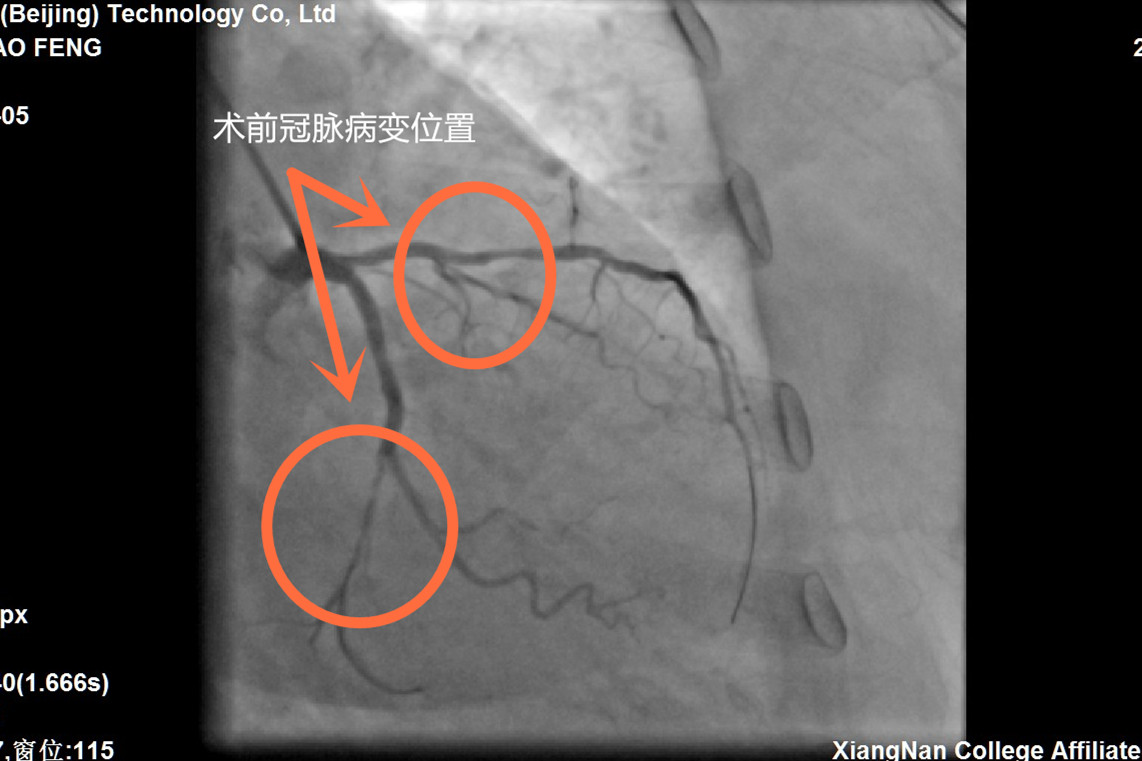

本网讯(通讯员 李华锋)7月5日,67岁的段大妈(化名),因胸痛一周前往湘南学院附属医院心血管内二科住院治疗,行冠脉造影提示左前降支近段重度狭窄、左回旋支远段重度狭窄,李维军主任医师手术团队经与患者沟通病情,建议行冠脉血运重建术。